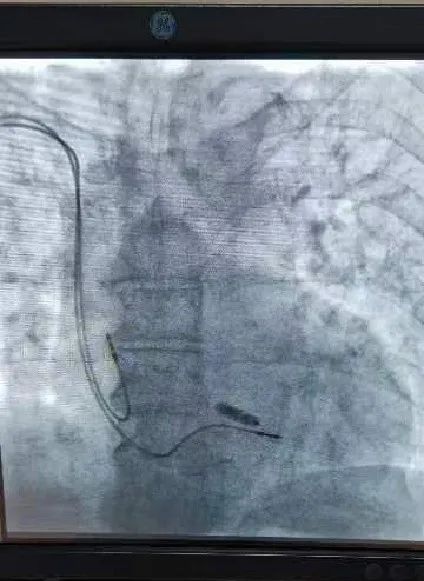

无导线起搏器成功植入

在哈医大二院李述峰老师的指导下,手术在局部麻醉下进行,通过股静脉穿刺,将起搏器通过导管植入到心腔内部,手术时间仅有30分钟,患者术后反应良好,两天后即可恢复正常的工作和生活。